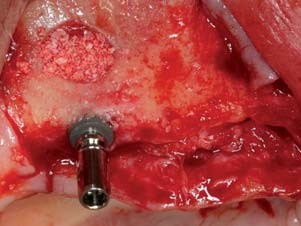

Im August 2012 wurden bis auf Zahn 38 alle Zähne extrahiert. Nach einer Ausheilzeit von zwei Monaten erfolgte der implantatchirurgische Eingriff. Für den Oberkiefer waren sechs und für den Unterkiefer vier Implantate geplant. Weng et al.⁷ haben in einer Studie gezeigt, dass eine Teleskopprothese auf nur zwei Pfeilern im Eckzahnbereich des Oberkiefers, ob zahn- oder implantatverankert, keine gute Prognose hat. Die exakte Position und Ausrichtung der Implantate wurde mittels laborgefertigter Positionierungsschablonen, die anhand der Wachsaufstellungen angefertigt worden waren, festgelegt und kontrolliert. Die Ankylos A und B Implantate (Dentsply Implants, Mannheim) mit 3,5 und 4,5 mm Durchmesser sowie 9,5 und 11 mm Länge wurden in Regio 12, 14, 16, 22, 24, 26 sowie 32, 34, 42 und 44 eingebracht. Dabei musste im Oberkiefer der Alveolarkamm geglättet und im anterioren Bereich horizontal erweitert werden. Dies geschah mittels Bone Splitting. Ferner wurde bei Regio 16 ein externer Sinuslift vorgenommen. Amalgamablagerungen der alten WSR in der Unterkieferfront wurden während des Eingriffs entfernt. Die Implantate heilten gedeckt ein (Abb. 3–10).